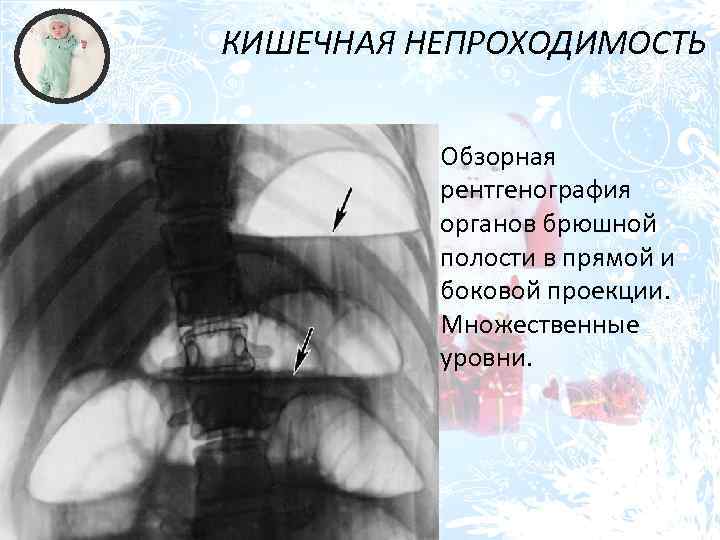

Нормы обзорной рентгенографии брюшной полости